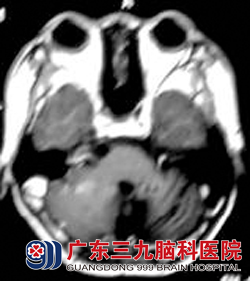

来院时司徒精神倦怠,表情痛苦,眼底检查见双侧视乳头水肿边缘不清,走路不稳。头颅MR显示后颅窝占位,考虑髓母细胞瘤。完善相关检查后行肿瘤切除术,术后病理证实为髓母细胞瘤。

治疗前。 治疗8年后复查。